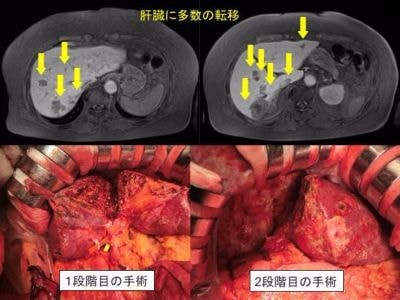

【大腸がんの多発肝転移について】

最近、食事の欧米化にともない大腸がんが増加し、男性ではがん死亡の3位、女性では1位になっています。大腸がんの治療ガイドラインでは、大腸がんの肝転移は、根治手術が可能な場合は、他の治療方法(抗がん剤など)とくらべて、手術が良好な成績であると明記されています。ただし、肝臓に数多く転移がある場合も少なくありません。切除の可能性を診断するためには専門的な知識が必要であるため、肝臓外科専門施設でなければ、本当は手術できる状態なのに手術できないと判断される場合があります。当院では、多発転移肝がんであっても、さまざまな工夫を用いて、切除を行っています。滋賀医科大学附属病院では日本で施行している施設が少ないアルプス(Associating Liver Partition and Portal vein embolization for Staged hepatectomy; ALPPS)手術にも取り組んでいます。ぜひ一度、ご相談ください。